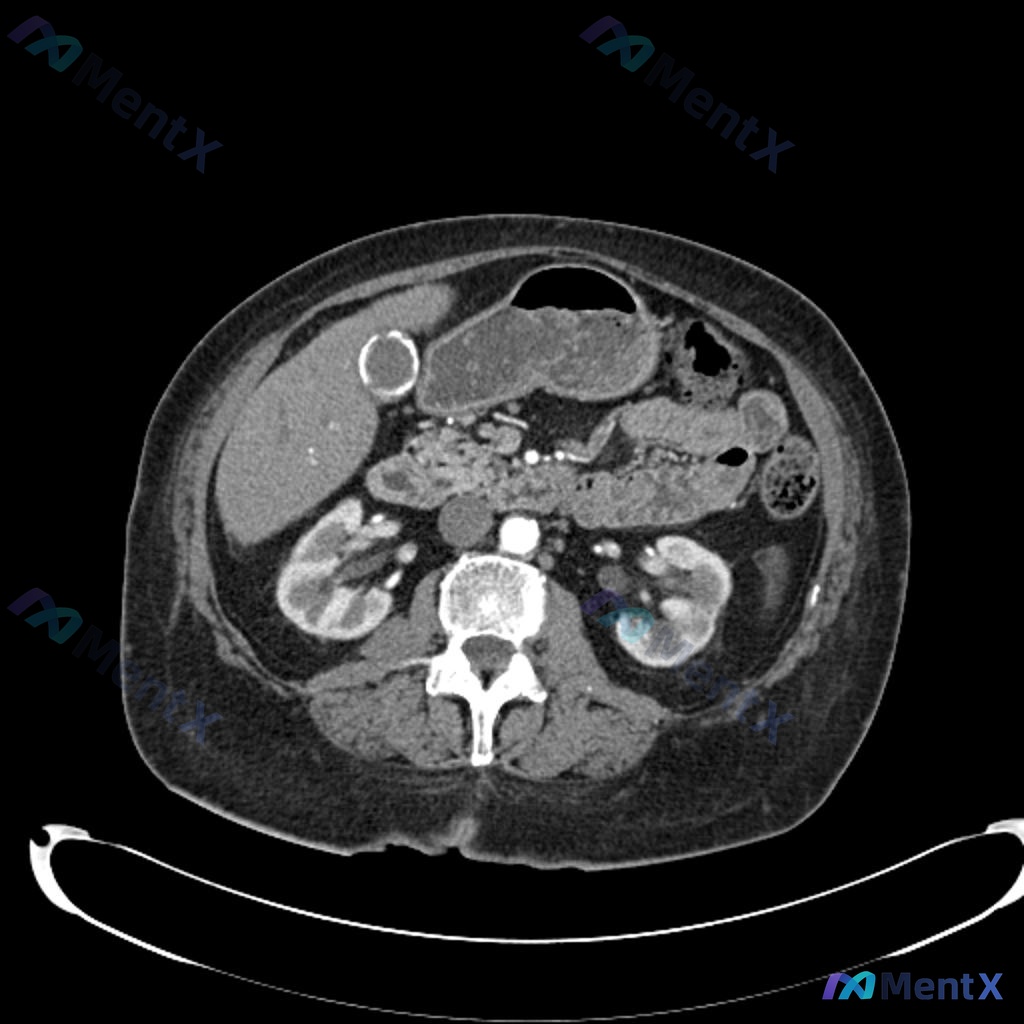

- 因为左下腹疼痛做了腹部CT(影像提示胆囊壁环形钙化,即「瓷胆囊」)

- 显眼的影像发现:CT明确报了「瓷胆囊」,这是个和胆囊癌风险相关的慢性病变

结论:直接排除瓷胆囊导致本次急症

整体看下来,瓷胆囊是个偶然发现的「背景板」病变,真正需要关注的是创伤相关的隐匿性损伤。

至于瓷胆囊本身,等这次外伤完全好了之后,再去肝胆外科评估择期手术就行(毕竟和胆囊癌风险相关),但这绝对不是现在的任务。